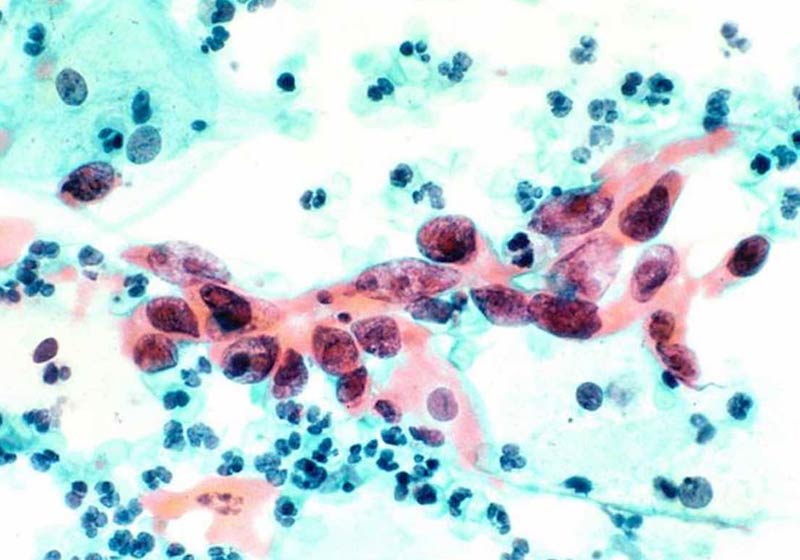

Tratamento contra câncer – Foto: National Cancer Institute